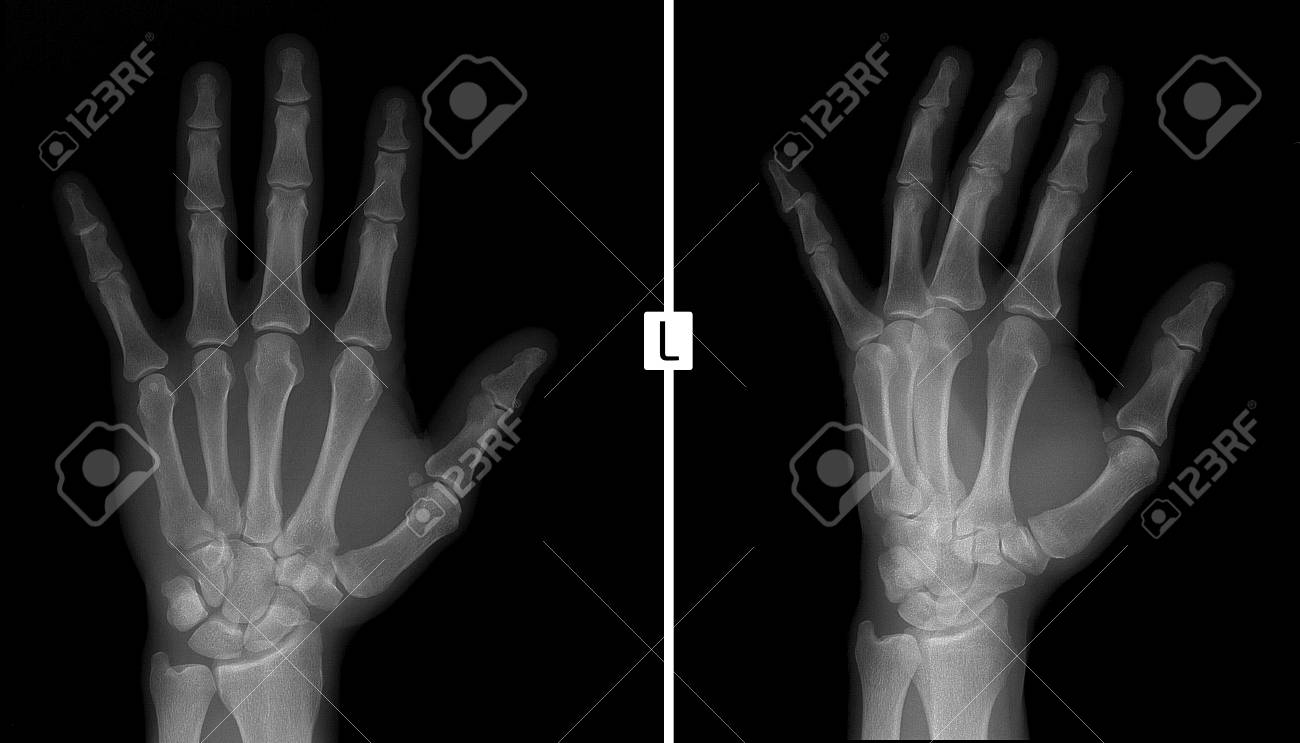

結果は同じで足の親指「末節骨骨折」 基本的に足の指の骨折は、骨片(破片)が関節内に挟まったりしない限り、 手術等は行わず、保存的に固定をして経過を診ることが多いです。 だからといって放っておくと、指が変形したり、痛みで歩き方が長期間基節骨骨折・末節骨骨折など指骨骨折とは 指には末節骨、中節骨、基節骨の3種類の骨があります。 母指(おやゆび)には中節骨はなく末節骨、基節骨の2つだけで、他の4本には3つの骨があります。 指には3種類の骨があります。 婚約者が仕事中に、右手示指末節骨開放骨折をしました。 0kg のドラム缶と地面の隙間に指先を挟みました。 手指専門医がいる整形外科で、すぐに治療を受けました。 骨はレントゲンでは、斜めにスパッと折れていました。 専門医からは、骨はくっつくと思うと言われました。 右示指末節骨

末節骨 末節骨は短骨に分類され、末節骨は左右の手足に5本ずつあり、人体では合わせて個の末節骨があります。 (中節骨は親指にはないので計16個) 手の指の骨は、中手骨があり指骨(基節骨・中節骨・末節骨)と続き、足の指の骨は中足骨から趾骨(基節骨・中節骨・末節骨)となります。指の骨は,中手骨と指骨に分けられます。 中手骨は,手根骨に近い方であり指骨は指先の方です。 指骨は,基節骨・中節骨・末節骨に分けられます。 後遺障害(後遺症)となるのは,指骨骨折によって指関節が損傷されて可動域制限が残る場合です。 末節骨骨折(Distal phalanx fracture)について。末節骨(=蹄骨:Coffin bone、Pedal bone)の骨折は、競走馬(特にスタンダードブレッド)に多く見られ、その八割が前肢に発症します。末節骨骨折は、タイプ1~7の病態に分類され、骨折のタイプに応じて、様々な治療法が推奨されて

手根骨と手指の解剖について 救急外来 舟状骨骨折と月状骨脱臼に注意 研修医 救急医のための整形外科 外傷 スポーツ医学マニュアル